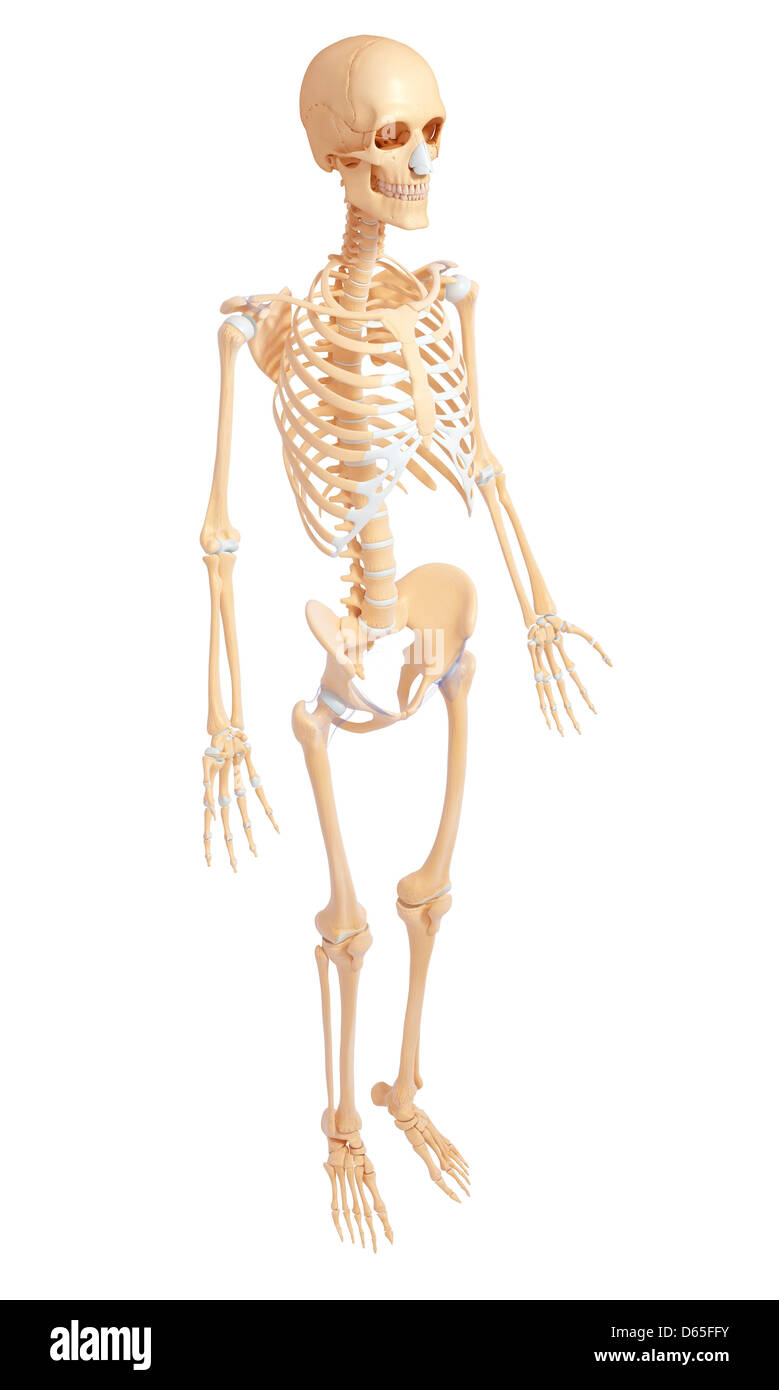

Du côté de l'anatomie du squelette Banque D'Imageshttps://www.alamyimages.fr/image-license-details/?v=1https://www.alamyimages.fr/photo-image-du-cote-de-l-anatomie-du-squelette-55441007.html

Du côté de l'anatomie du squelette Banque D'Imageshttps://www.alamyimages.fr/image-license-details/?v=1https://www.alamyimages.fr/photo-image-du-cote-de-l-anatomie-du-squelette-55441007.htmlRFD65FFY–Du côté de l'anatomie du squelette